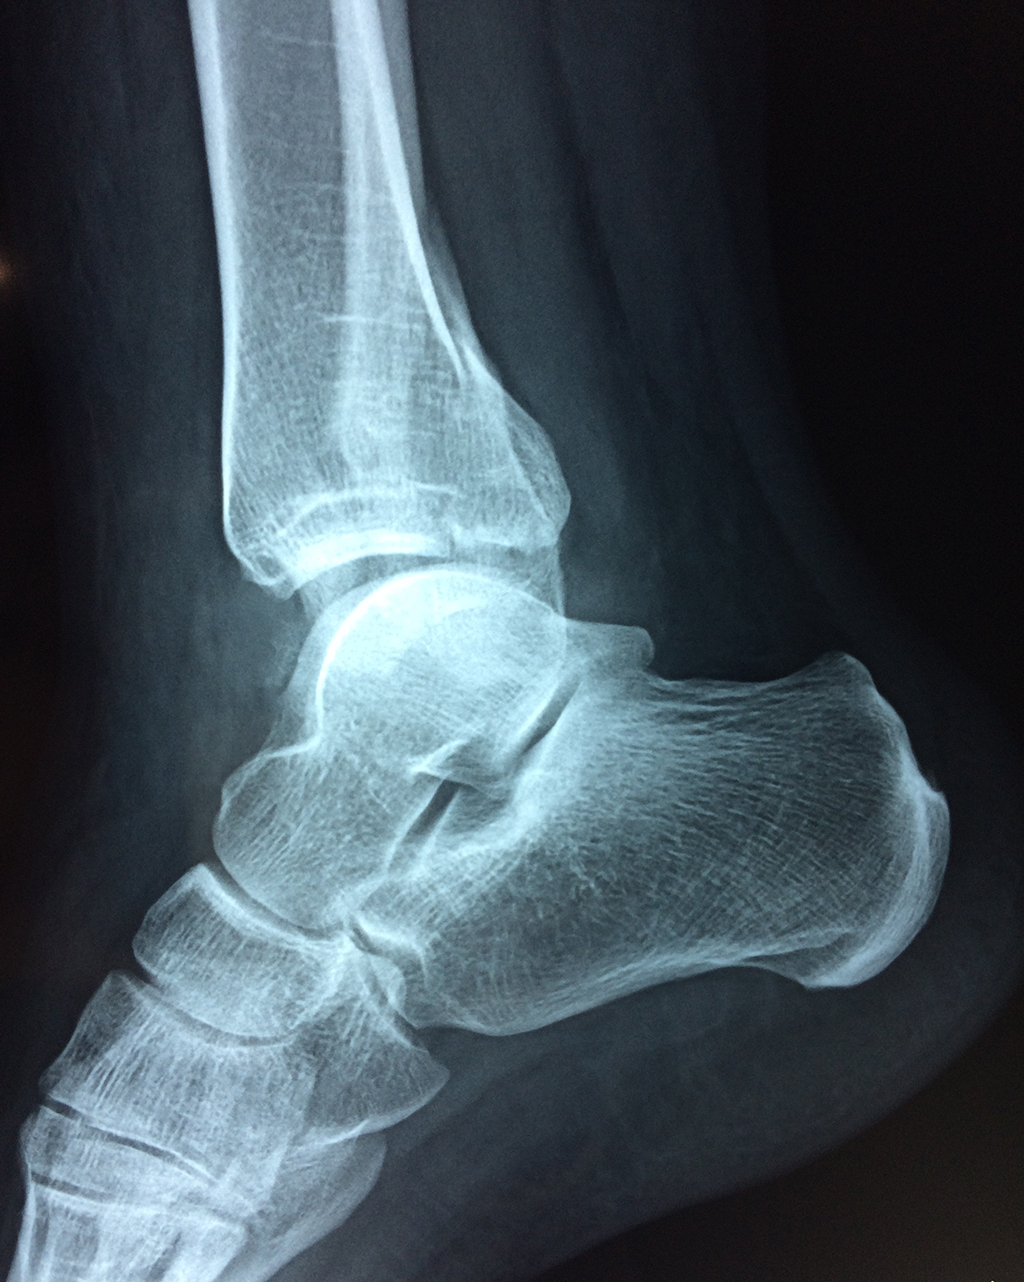

Una fractura de tobillo es la rotura de uno o más de los huesos del tobillo. Estas fracturas pueden ser:

Algunas fracturas de tobillo pueden requerir cirugía si: